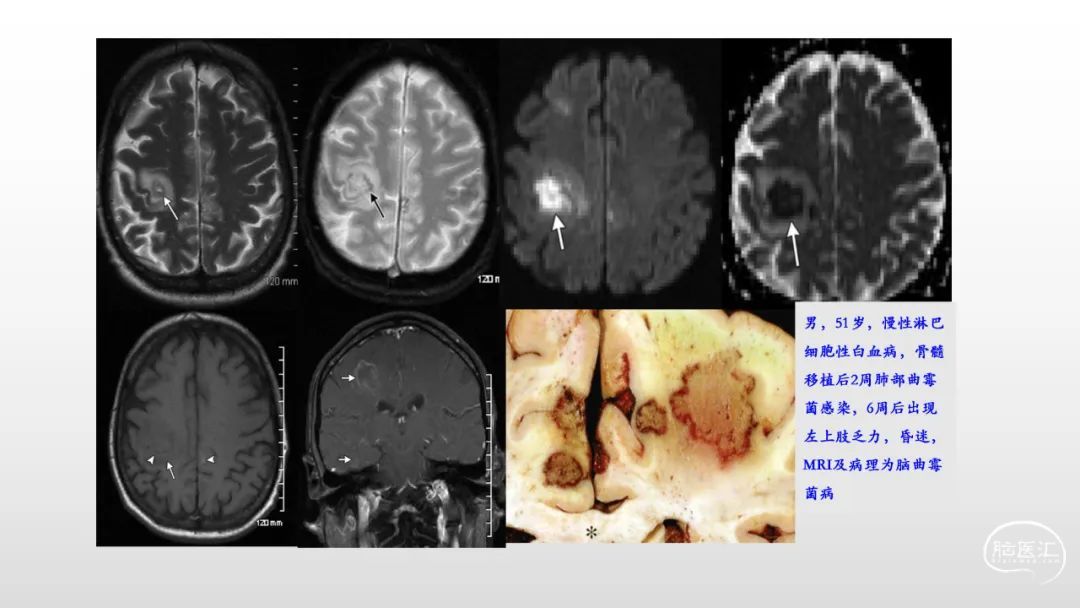

颅脑影像诊断基础知识讲座:感染和免疫性疾病1